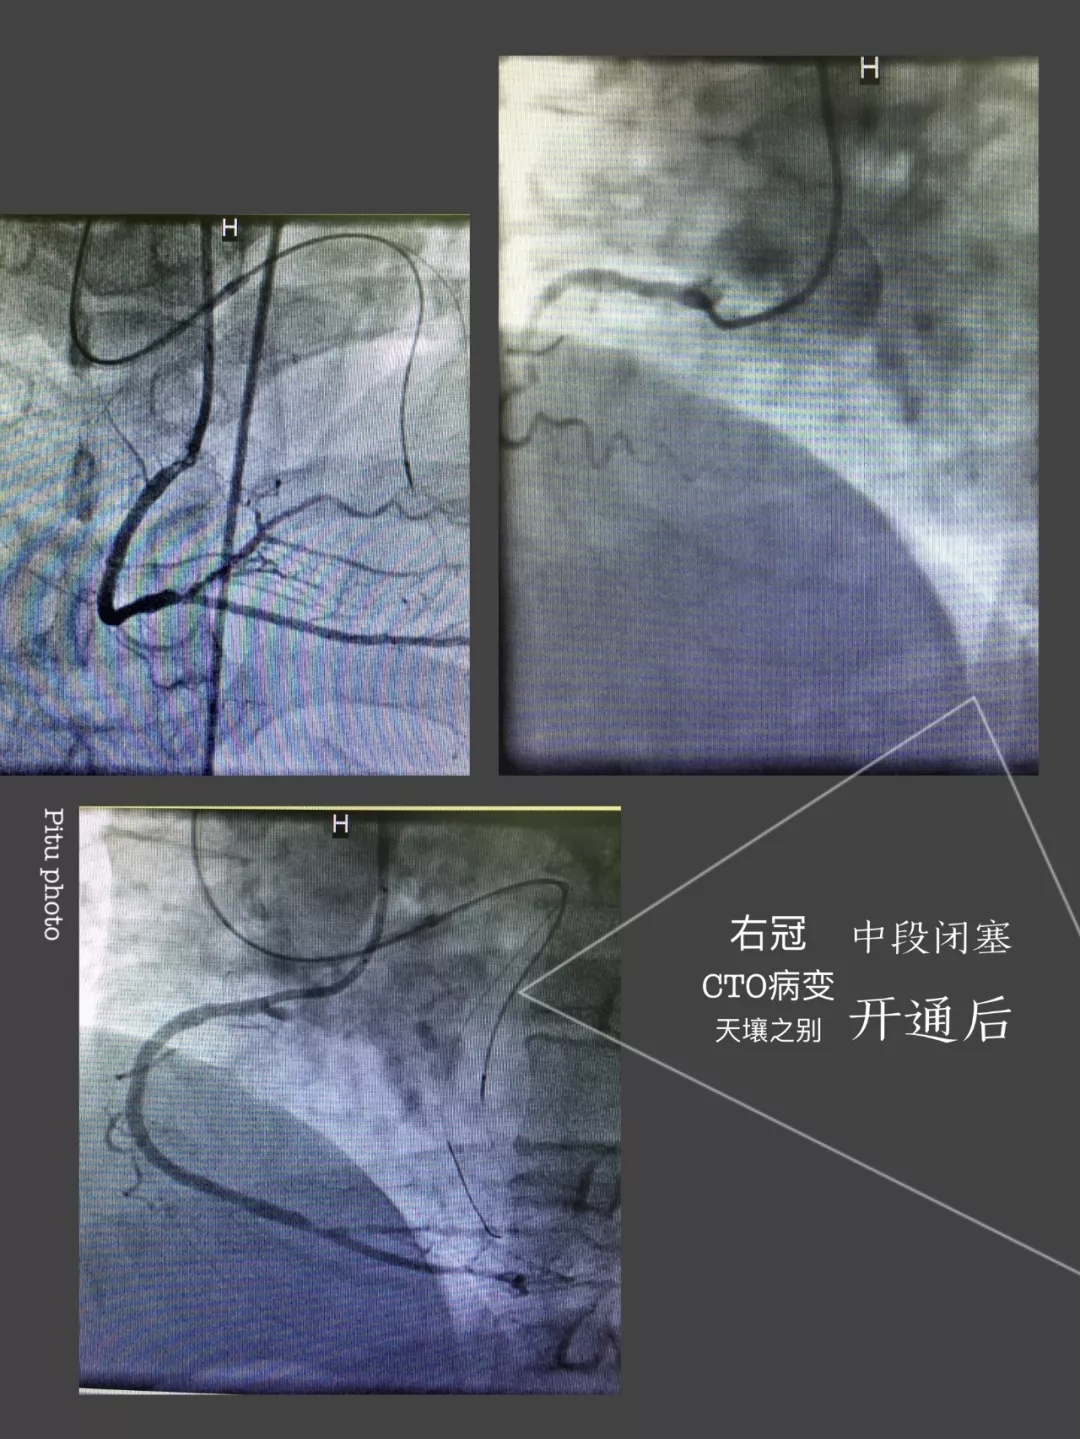

心内三完成成人导航首例逆向开通冠脉CTO病变